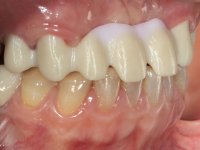

The patient did not like her smile, said that she had "very artificial looking teeth".

Female patient, 43 years old non-smoker. After a clinical and imaging examination, the patient presented teeth 1.7 / 1.4 / 1.3 / 2.2 / 2.3 / 2.4 / 2.6 with endodontic treatment in the upper jaw, showing absence of teeth 1.6 / 1.5 / 1.2 / 1.1 /2.1 and 2.5, and was rehabilitated with a 10-element monobloc metal-ceramic bridge. The anterior maxilla presented extensive vertical and vestibular bone reabsorption. In the lower jaw, two implants were placed at the site of teeth 4.6 and 4.5 rehabilitated with a metal-ceramic bridge. Teeth 3.6 and 3.7, with endodontic treatment, were rehabilitated with intra-radicular posts and a two-element metal-ceramic bridge. The antero-inferior teeth presented class III and IV resin restorations. Tooth 3.5 was absent. The patient had a vertical dimension of occlusion reduction, accompanied by accentuated dental wear and some ceramic fractures. Good oral hygiene.

In view of the clinical situation, oral rehabilitation was proposed to improve the aesthetic appearance, but also to solve the lack of posterior teeth, seeking a functional and aesthetic rehabilitation. The plan included replacing the metal-ceramic bridge by a bridge with Zr infrastructure coated with coronary and gingival ceramics. The edentulous area of the first quadrant would be rehabilitated with 2 implants and a bridge of two elements. It was intended with this treatment plan, to recover the vertical dimension of the occlusion and to reshape the dental anatomy, thus creating a more natural aesthetic appearance.

Alginate impressions were made at both arches arcades, accompanied by intermaxillary registration relations and collecting information with facial bow facial bow. In the laboratory, a provisional bridge with 13 elements in autopolymerizable acrylic was built, in which a metallic reinforcement was included. Teeth 1.7 / 1.4 / 1.3 / 2.2 / 2.3 / 2.4 and 2.6 were used as pillars. The metal-ceramic bridge was removed after performing longitudinal cuts with diamond burs. The dental abutments were reprepared and the temporary bridge was relined in the mouth with self-curing acrylic. After confection of the provisional bridge, a gingival epithesis was made using composite resin with gingival tonality in order to function as a mock-up, which allowed the patient to preview the possibility of using gingiva shade ceramics in the final work. This option was approved by the patient. Subsequently, the placement of two implants in the first quadrant was planned and executed. The provisional monoblock was removed for placement of the implants, and after surgery was again cemented provisionally. After the osseointegration period, the impressions were made to the maxilla. In the anterior zone, impregnated gingival retraction cords were used, and in the posterior areas, kaolin paste was used. Implant printing utilized the open tray technique. The printing material used was soft and regular putty addition silicone, both fast-setting. In the laboratory, the model of provisional restorations and the gingiva epithesis mock-up served as orientation for waxing the infrastructure. The plaster work model and the waxing of the infrastructure were placed in a laboratory scanner and yielded a digital work model, in which the scanning of the waxed infrastructure was superimposed. This overlay facilitated the CAD design of the Zr infrastructure. Subsequently, the CAD drawing for a CAM milling process provided the Zr pieces. The infrastructure was pigmented with a pinkish coloration, which favors the subsequent placement of gum shade ceramic. During the modeling of the infrastructure, the need to increase the occlusal wear on tooth 1.4 was detected. This was done in the real working model cast and an acrylic wear control guide was created, which accompanied the proof of the infrastructures. Corrective wear and Zr parts test were performed in mouth. During the test, the color choice of the gum shade ceramic was reassessed. The treatment was finished in the laboratory, and after approval by the patient, was definitively placed in the mouth.